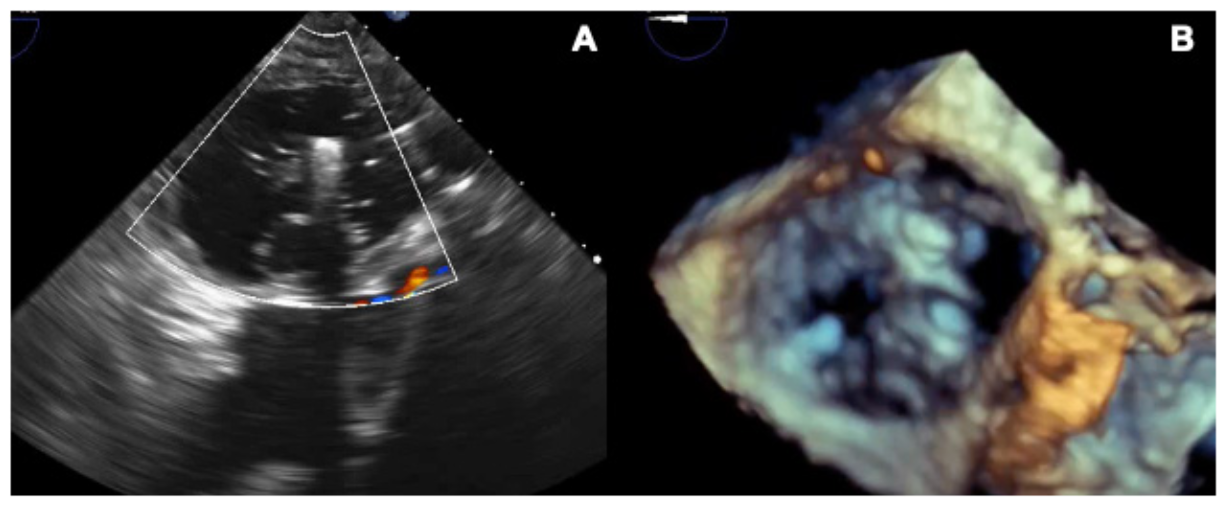

Under transesophageal echocardiography guidance, we attempted to grasp the anterior and septal leaflets. However, grasping was not initially successful. The clip was moved and deployed centrally, spanning the septal leaflet on one side and anterior and posterior leaflets close to the anteroposterior commissure on the other (Figure 1). Tissue grasping was checked and confirmed. Excellent final result was obtained with triple orifice creation (Figure 2) and mild residual regurgitation (Video Series).